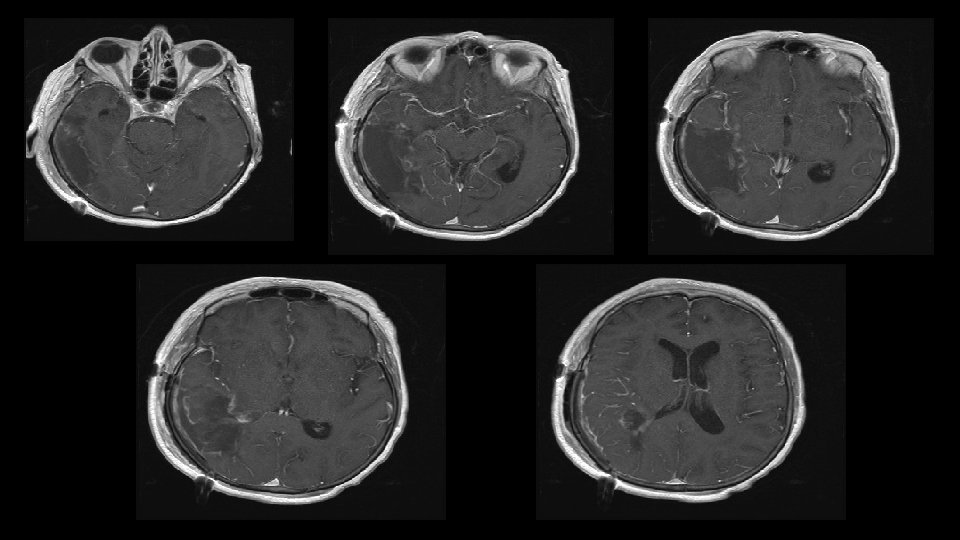

GROSS TOTAL RESECTION (GTR)

Glioblastoma always recurs December 2010 March 2011